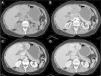

HHs are suspected when ultrasonography shows nodules with homogeneous hyperechogenicity, but additional imaging tests, usually triphasic computed tomography (TCT) or magnetic resonance imaging (MRI), are required to confirm the diagnosis due to the lack of specificity of ultrasonographic findings. TCT typically reveals progressive enhancement during the arterial phase in a centripetal fashion. MRI shows a low signal intensity on T1-weighted images, high signal intensity on T2-weighted sequences, and an inward enhancement after gadolinium administration can be seen.14 Tc-99m-labeled red blood cell single emission photon computed tomography may be helpful when there is diagnostic uncertainty; it has sensitivity, specificity and accuracy of 97%, 83%, and 96%, respectively.15 Positron emission tomography is useful to differentiate heterogeneous HH from angiosarcomas.16 The differential diagnosis includes angiomatosis, metastases, hematic cyst, hepatic peliosis, and hepatocellular carcinoma, among others.

MethodsWe performed a retrospective analysis of patients with HH at our hospital within the time frame of January 1, 1990 and November 31, 2008. We made an electronic search regarding outpatient and inpatient hospital records looking for the diagnosis of hemangioma and/or benign hepatic tumor, which corresponded to the D 18.0 and D 13.4 categories of the CIE 10, respectively. We included all patients with GHH and HH, and diagnosis was based on the presence of conclusive imaging findings on TCT or MRI (peripheral nodular enhancement in the early phase followed by centripetal enhancement during the late phase) (figs. 1-4) or on the histopathology report. Medical records were reviewed for each patient to obtain demographic, clinical, radiological, and laboratory information, evolution, and treatment; if surgery was performed, data regarding the type of surgery, duration, complications, and transfusion requirements were recorded. Pain due to HH was defined as persistent pain in the upper right abdomen that could not be better explained by an alternative diagnosis, including irritable bowel syndrome.

Triphasic Computed TomographyA 16 or a 64-slice multidetector CT (Somatom, Sensation 16 or 64; Siemens Munich, Germany) was used; images were obtained with a section thickness of 3-5mm and a reconstruction interval of 2-2.5mm. All cases were analyzed on a workstation with the capacity to produce coronal reformatted images. All patients received both intravenous and oral contrast. For intravenous contrast, 120ml of Conray (Mallinckrodt Baker Inc., St Louis Missouri, USA) was given 45 s prior to performing the scan; for oral contrast, 40ml of Ioditrast M60 (Justesa Imagen Mexicana) were diluted in 1,000ml of water and given to all patients orally one hour prior to computed tomography. All TCT images were analyzed by at least 2 certified radiologists.

Magnetic resonance imagingMagnetic resonance imaging (MRI) was performed on a 1.5 T system (Signa Excite HD, GE Healthcare, Milwaukee, USA), using a variety of software upgrades that evolved during the study period. Standard liver imaging sequences included T1-weighted In-phase and Opposed-phase gradient echo and T2-weighted fast spin echo sequences. T1-weighted imaging was repeated after contrast material administration during hepatic arterial (19-25 s), portal (40-45 s), venous (60-65 s) and delayed (3-5min) phases. Patients received Gadopentate Dimeglumine (Gd-DTPA [Magnevist, Bayer Schering Pharma]) at a mean dose of 0.1 mmol/kg of body weight, a unique bolus at a 1.5 - 2ml/s rate, followed by a saline flush (mean volume 20ml).